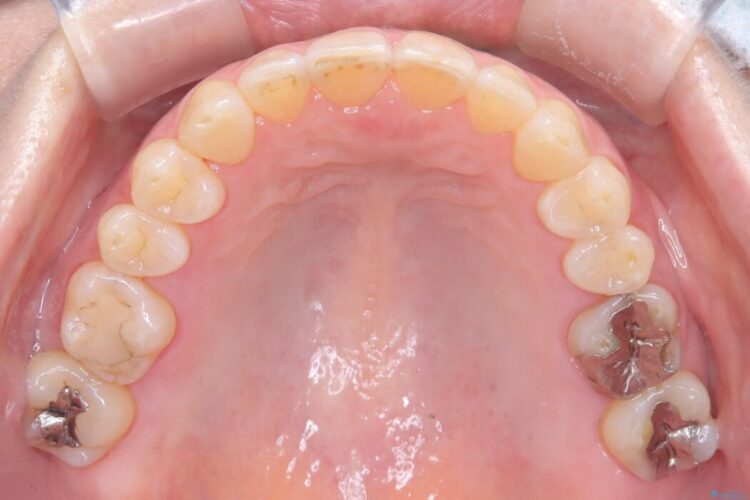

ワイヤー矯正ならではの確実な歯のコントロールにより、当初の計画通り約1年という短い期間で、前歯のガタつきが解消。見た目が美しく整っただけでなく、清掃しやすい機能的な歯並びを獲得していただけました。